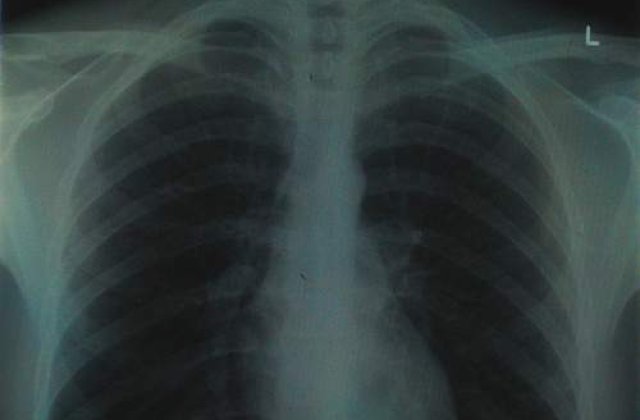

Vasili, acum in varsta de 80 ani, a fost socat dupa ce a efectuat un test de rutina care a inclus o fotofluorografie. Potrivit Descopera, medicul i-a spus ca a descoperit in plamanul sau drept o pata care ar putea fi un semn de tumoare canceroasa. Pacientul a fost trimis de urgenta la un centru oncologic unde a fost supus unor teste MRI. Medicul care i-a analizat ore in sir radiografiile l-a intrebat stupefiat daca a fost ranit in razboi. Vasili a replicat glumind ca era un copil in acea perioada. Medicul i-a spus foarte serios ca ceea ce parea la prima vedere o tumoare, nu era altceva decat un glonte. Trei zile mai tarziu batranul si-a reamintit o patanie din copilarie: "Cand eram mic obisnuiam sa ma joc cu cartuse de pusca. Eram in anul 1941. Un copil din vecini a gasit pe strada un cartus de calibru mic. Nu stiu cum am ajuns sa mi-l var singur in nas. Orice incercare de a-l scoate a fost sortita esecului. Intr-un final l-am aspirat cu putere in mine. Nu am simtit nicio durere sau jena, si mai tarziu am uitat cu totul de el", declara Simonov, citat de Pravda.

Glontele nu l-a deranjat timp de 68 de ani, interval in care Vasili a facut armata s-a insurat, a crescut 4 copii si s-a pensionat linistit. In prezent, are o sanatate de invidiat pentru varsta sa, nu bea si nici nu fumeaza.